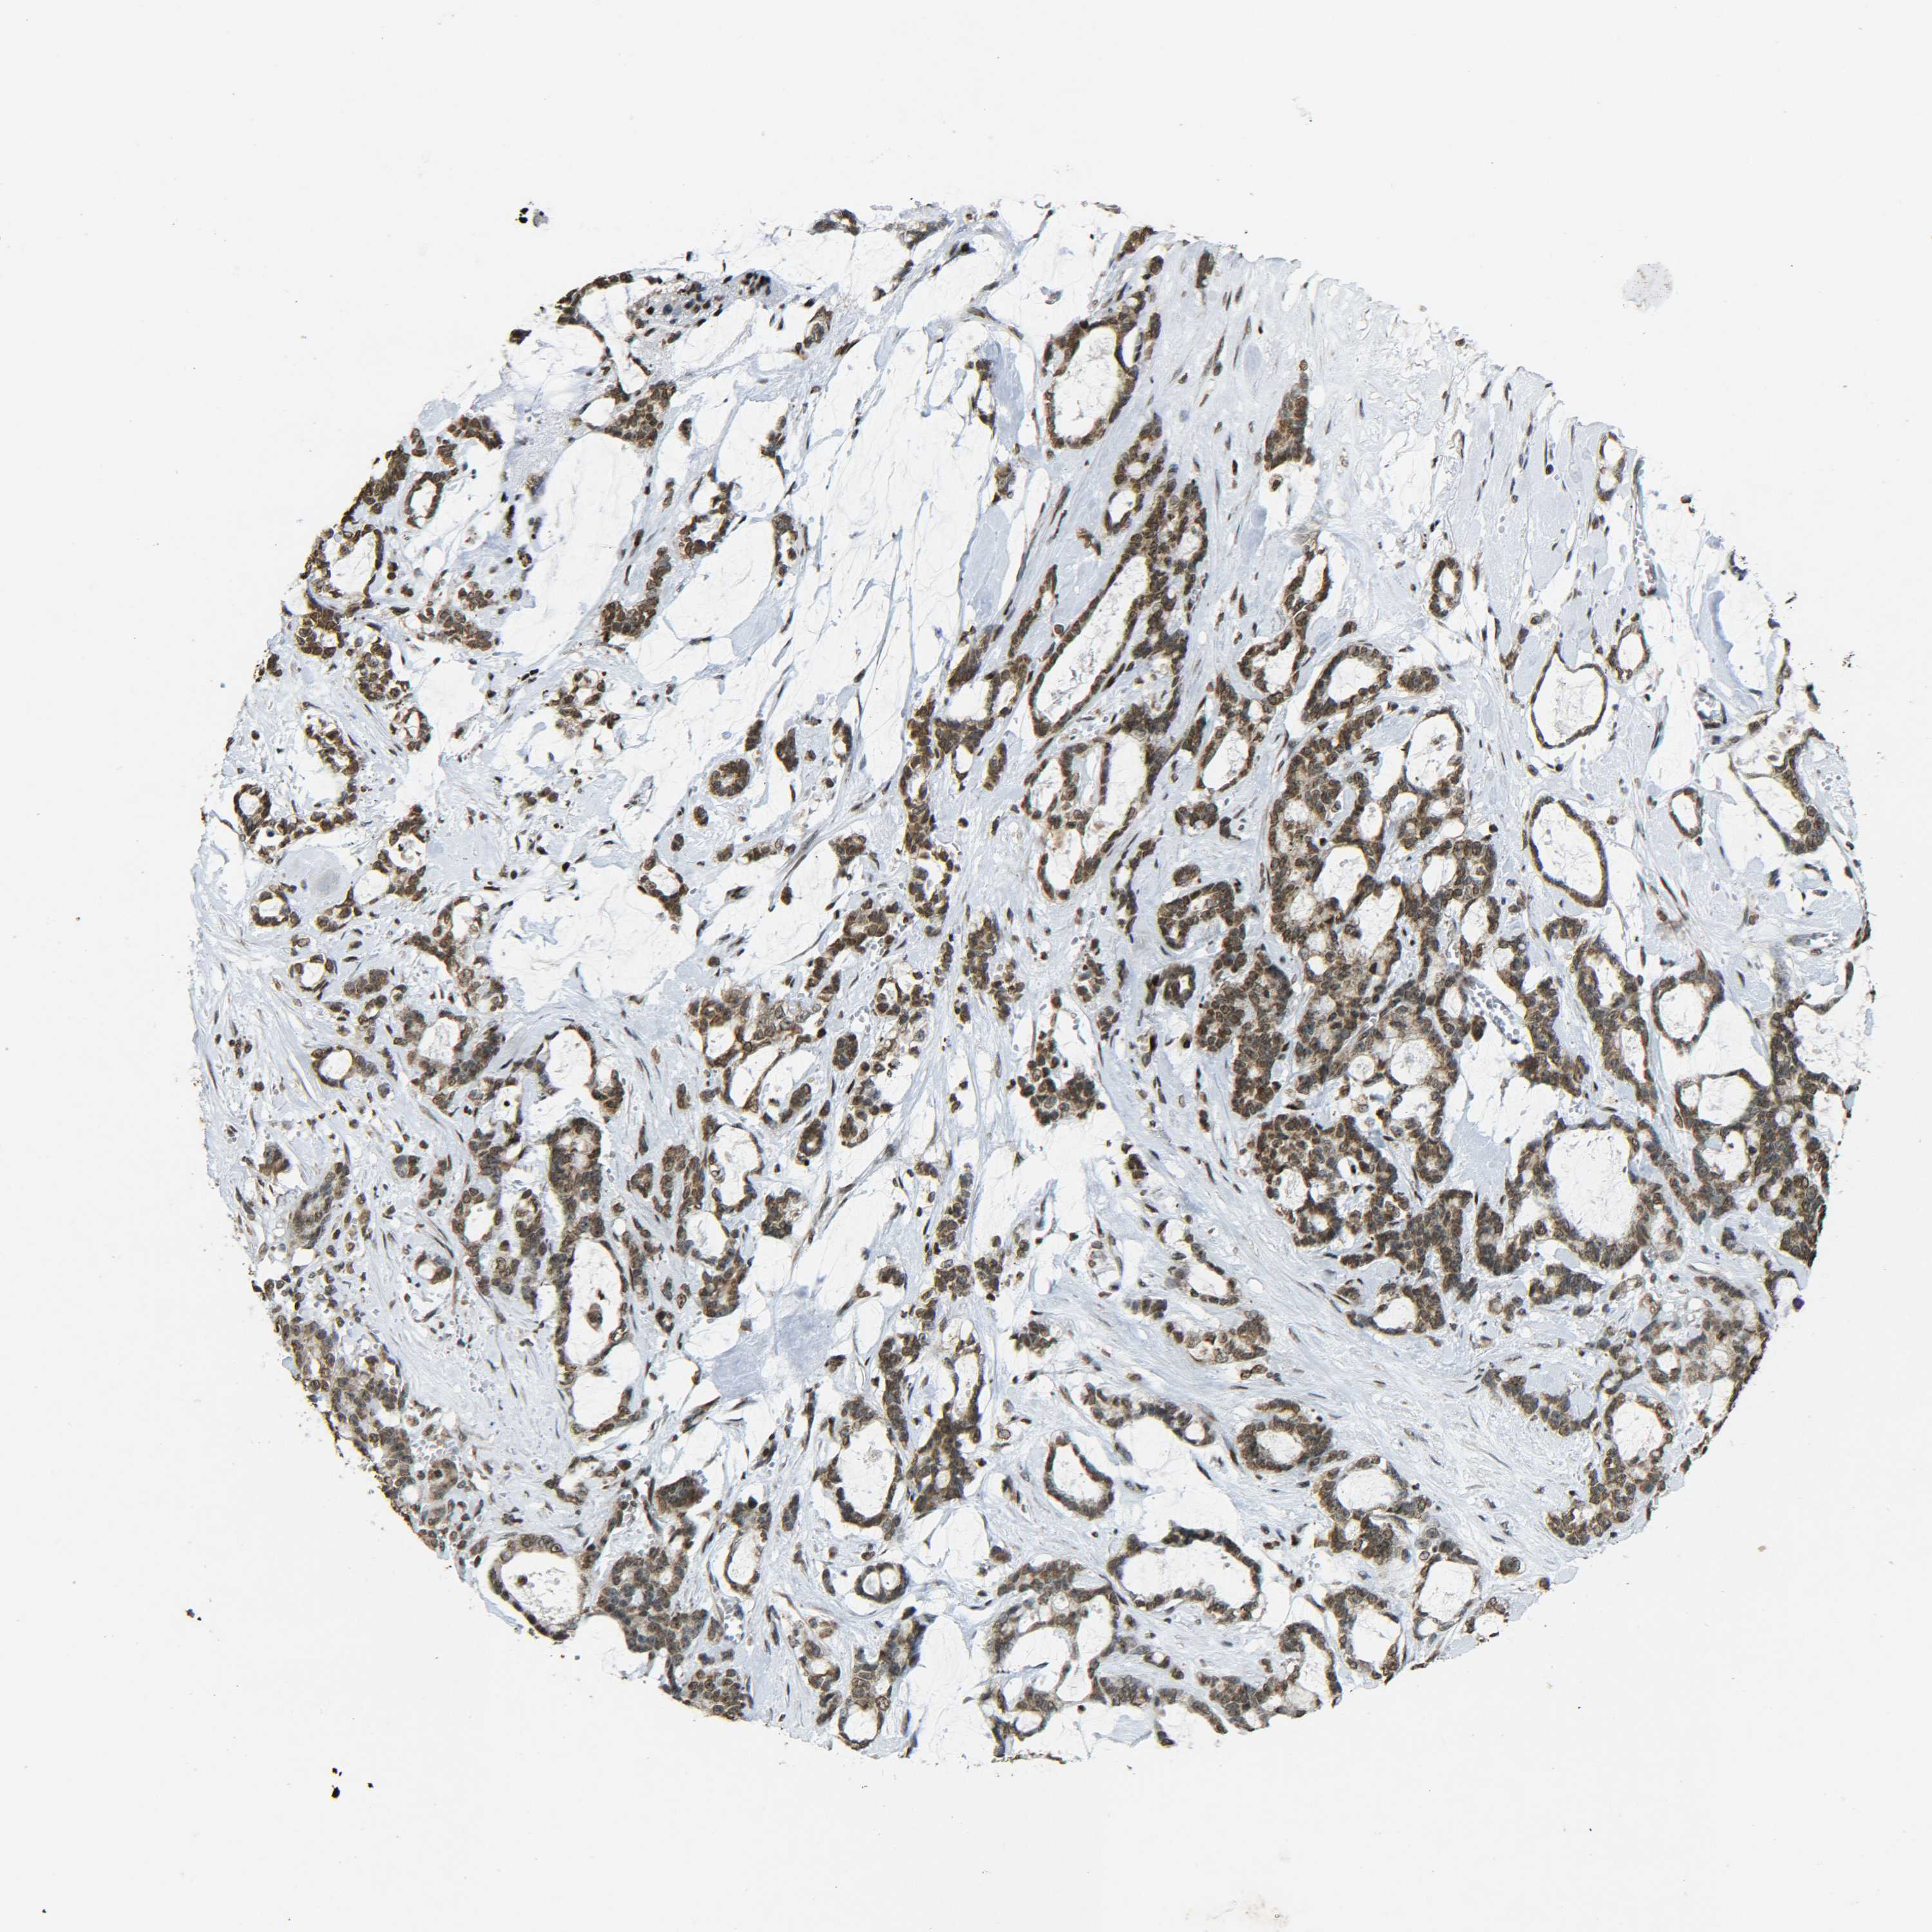

PANCREATIC CANCER - Protein expressioni

A mouse-over function shows sample information and annotation data. Click on an image to view it in a full screen mode. Samples can be filtered based on level of antibody staining by selecting one or several of the following categories: high, medium, low and not detected. The assay and annotation is described here.

Note that samples used for immunohistochemistry by the Human Protein Atlas do not correspond to samples in the TCGA dataset.

Antibody stainingi

Antibody staining in the annotated cell types in the current human tissue is reported as not detected, low, medium, or high, based on conventional immunohistochemistry profiling in selected tissues. This score is based on the combination of the staining intensity and fraction of stained cells.

Each image is clickable and will lead to virtual microscopy that enables deeper exploration of all samples and also displays staining intensity scores, fraction scores and subcellular localization as well as patient and tissue information for each sample.

Antibody CAB012342

Staining

High

Medium

Low

Not detected

Intensity

Strong

Moderate

Weak

Negative

Quantity

>75%

75%-25%

<25%

None

Location

Nuclear

Cytoplasmic/membranous

Cytoplasmic/membranous,nuclear

Adenocarcinoma, NOS

Adenocarcinoma, metastatic, NOS